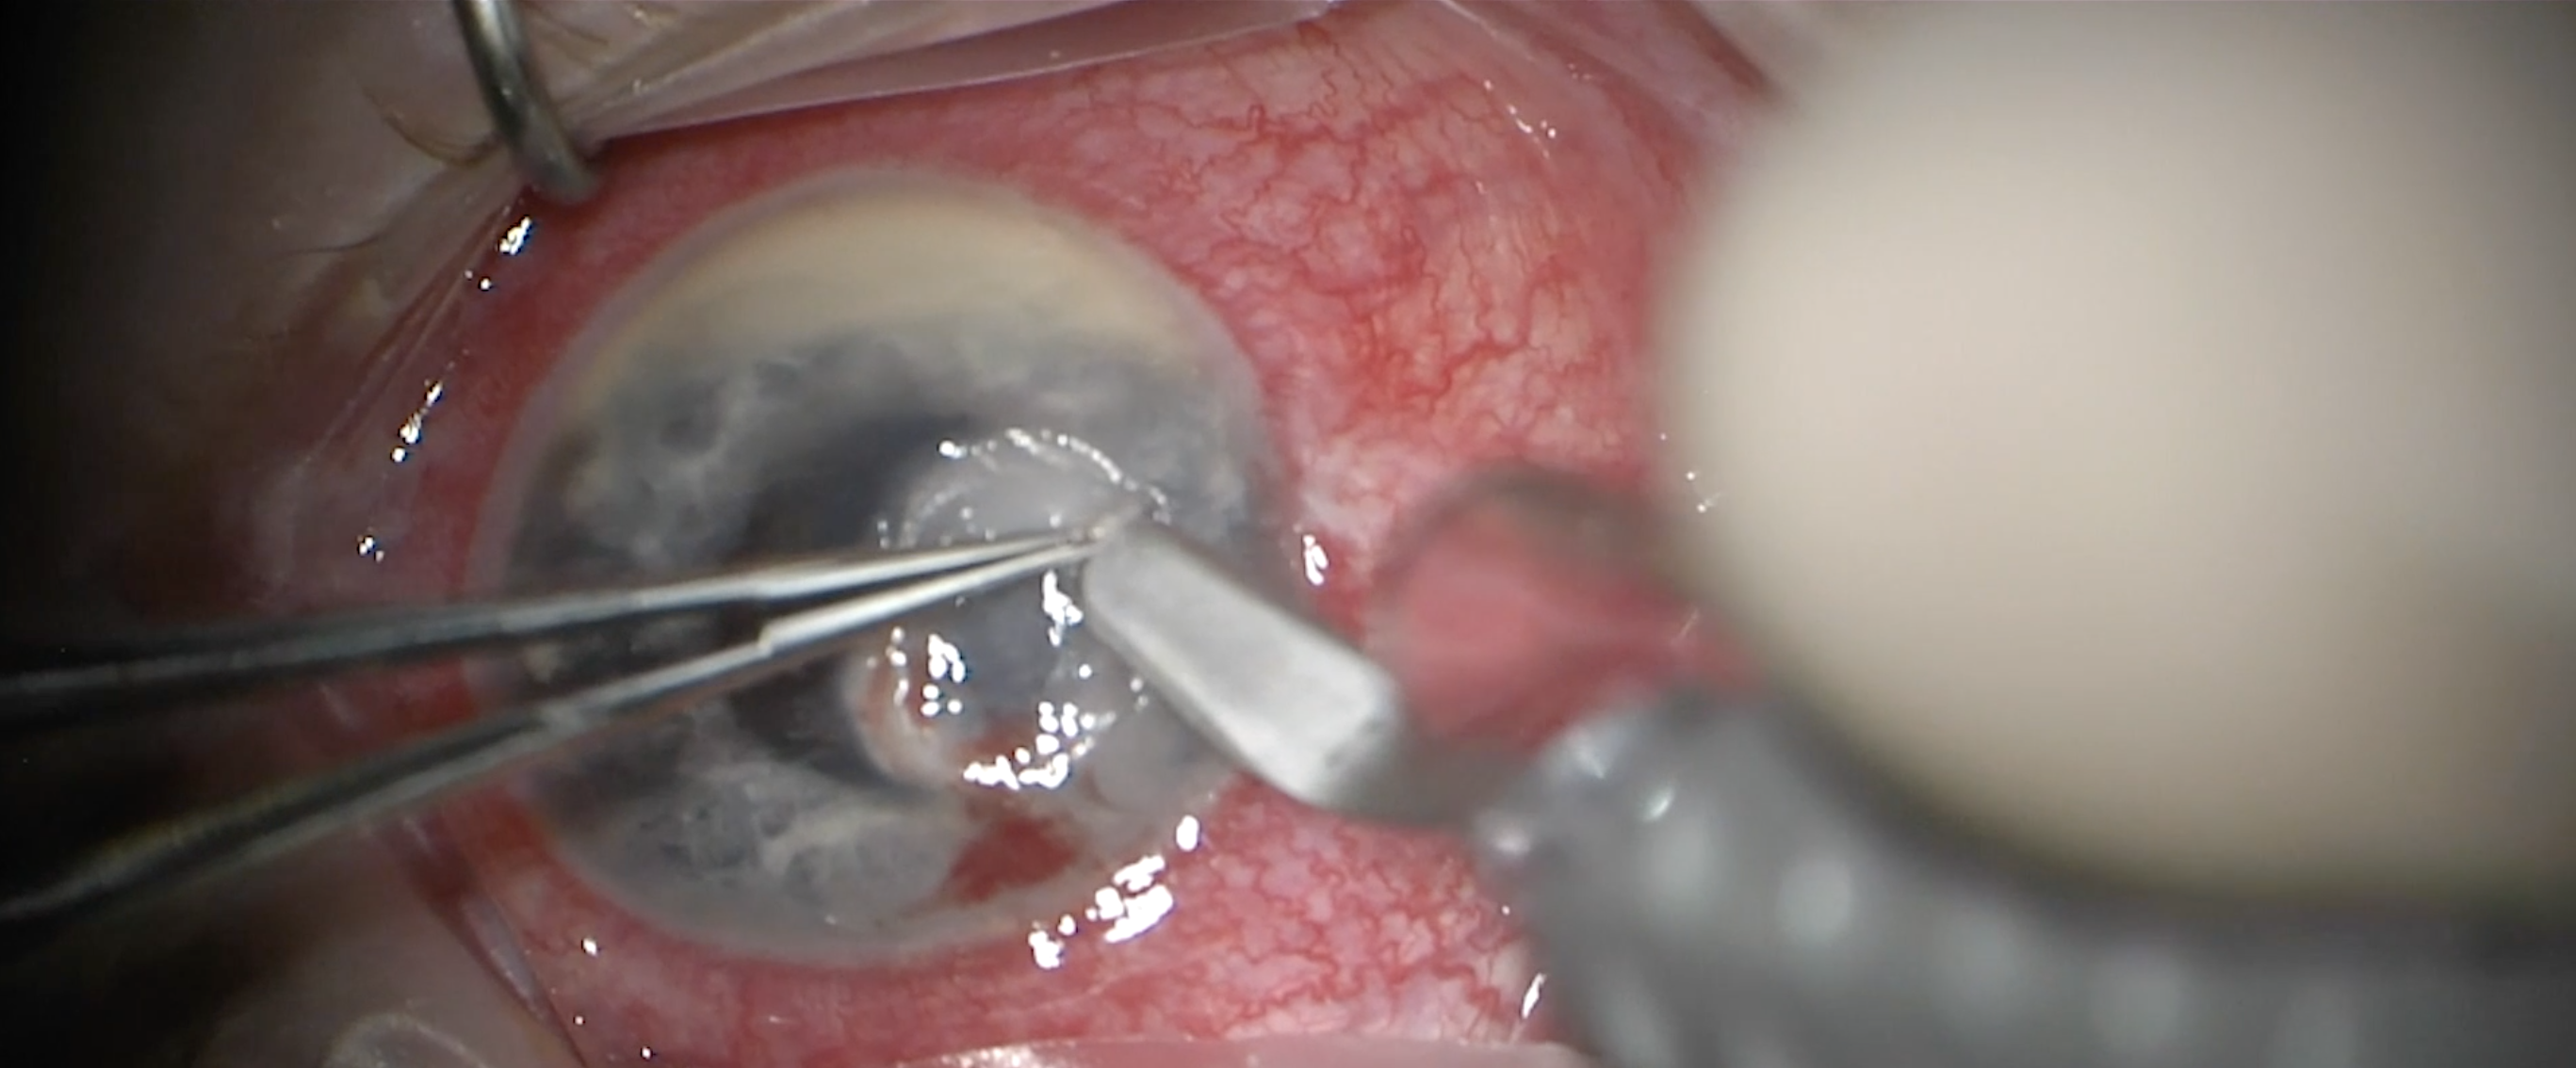

Abstract A patient presented with uncontrolled intraocular pressure (IOP) on maximum medical therapy and had bilateral laser iridotomy. The patient was diagnosed with angle-closure glaucoma. Biometry measurements were consistent with nanophthalmos. The right eye underwent phacoemulsification with a…

Nanophthalmos with Angle Closure Glaucoma A patient presented with uncontrolled intraocular pressure (IOP) on maximum medical therapy and had bilateral laser iridotomy. The patient was diagnosed with angle-closure glaucoma. Biometry measurements were consistent with nanophthalmos. The right eye und…